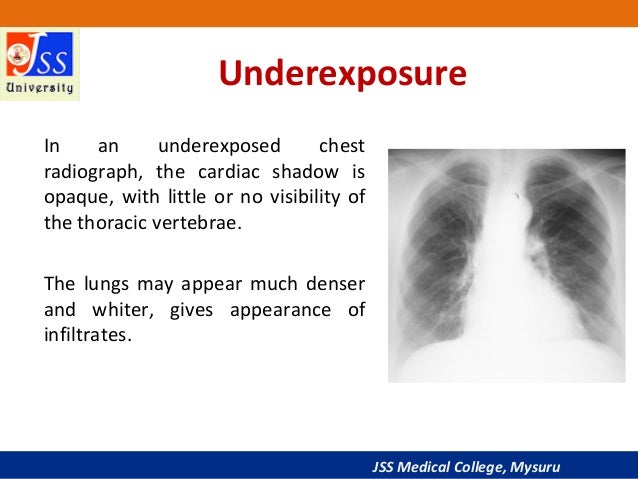

As long as the detector is not underexposed or greatly overexposed a diagnostic image will be displayed. Images will be displayed with the optimum density and contrast when the system has been set up with the required algorithm for chest imaging in our examination. One major advantage of digital radiography systems is the very wide exposure latitude. It’s the responsibility of the radiographer / technologist to select a technique that provides enough exposure to reduce the amount of noise while also adhering to ALARA/ALARP standards. Images should be repeated if relevant anatomical details or ability to see lines or endotracheal tubes in the mobile chest image cannot be distinguished because of poor positioning or exposure making the image undiagnostic. The 3-point scale for producing diagnostic images is: Image evaluation for exposure should perhaps be conducted using EI T is the EI for a given radiograph and the target exposure. Gross over exposure will result in ‘burned out’ pixels losing anatomical detail usually in the lungs. Underexposure can result in image noise, however, overexposed images will be displayed optimally on the display screen often at ten times the exposure. Digital systems generally display images with the optimum density and contrast regardless of the exposure factors. It is therefore important for the radiographer / technologist to understand Exposure Indicators (EI) and the Deviation Index (DI).